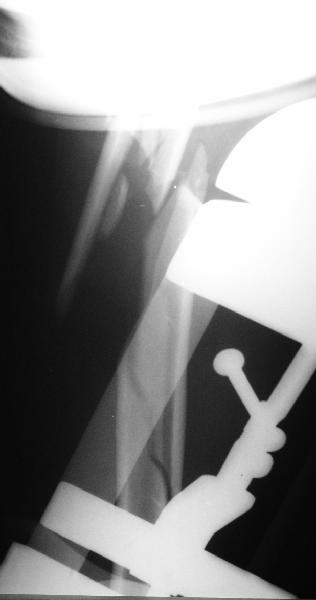

Well, to date he is still on abduction splint with traction applied to a wire placed through the olecranon. Images attached. The acetabulum

was ORIFed. The humerus is still discussing...